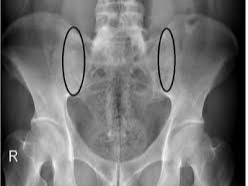

- 영상 검사: 엑스레이나 MRI를 통해 척추와 천장관절의 염증 및 손상을 확인합니다.